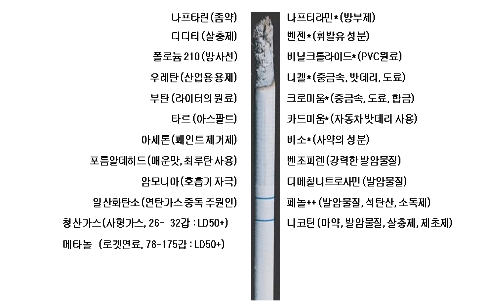

주요 담배 및 담배 연기 성분